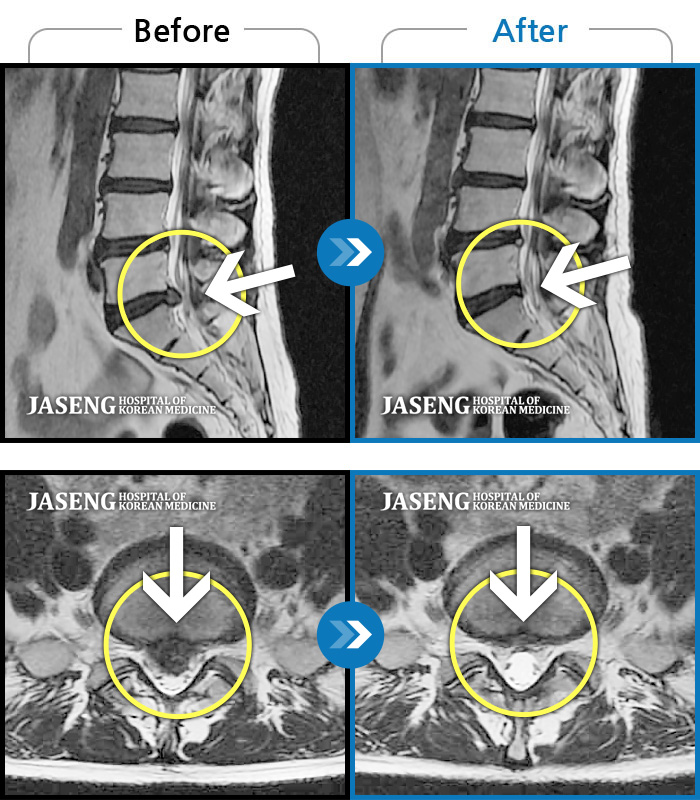

허리 골반 통증이 있고 다리가 저리고 아파 걷기가 힘들다.

2025.02.10 ~ 2025.09.13